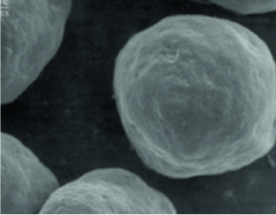

CaHA เป็นอนุภาคที่มีโครงสร้างทรงกลมเรียบที่มีขนาดเท่ากัน

การสร้างและฟื้นฟู ECM ( Extracellular Matrix ) โดยทำให้เส้นใยเซลล์สามารถทำงานได้ดีในรูปแบบอนุภาคที่มี ขนาดคงที่และพื้นผิวเรียบ

( ถ้าอนุภาคแหลมและไม่สม่ำเสมอ อาจเกิดการอักเสบ )

เรเดียส

(25~45um/Microsphere)

ผลิตภัณฑ์ A

(30~60um/Crystal)

ผลิตภัณฑ์ B

(20~80um/ไม่สม่ำเสมอ)

กระบวนการคงสภาพทรงกลม แสดงผลส่งเสริมการสร้างคอลลาเจนอย่างสม่ำเสมอโดยไม่ระคายเคืองต่อผิว